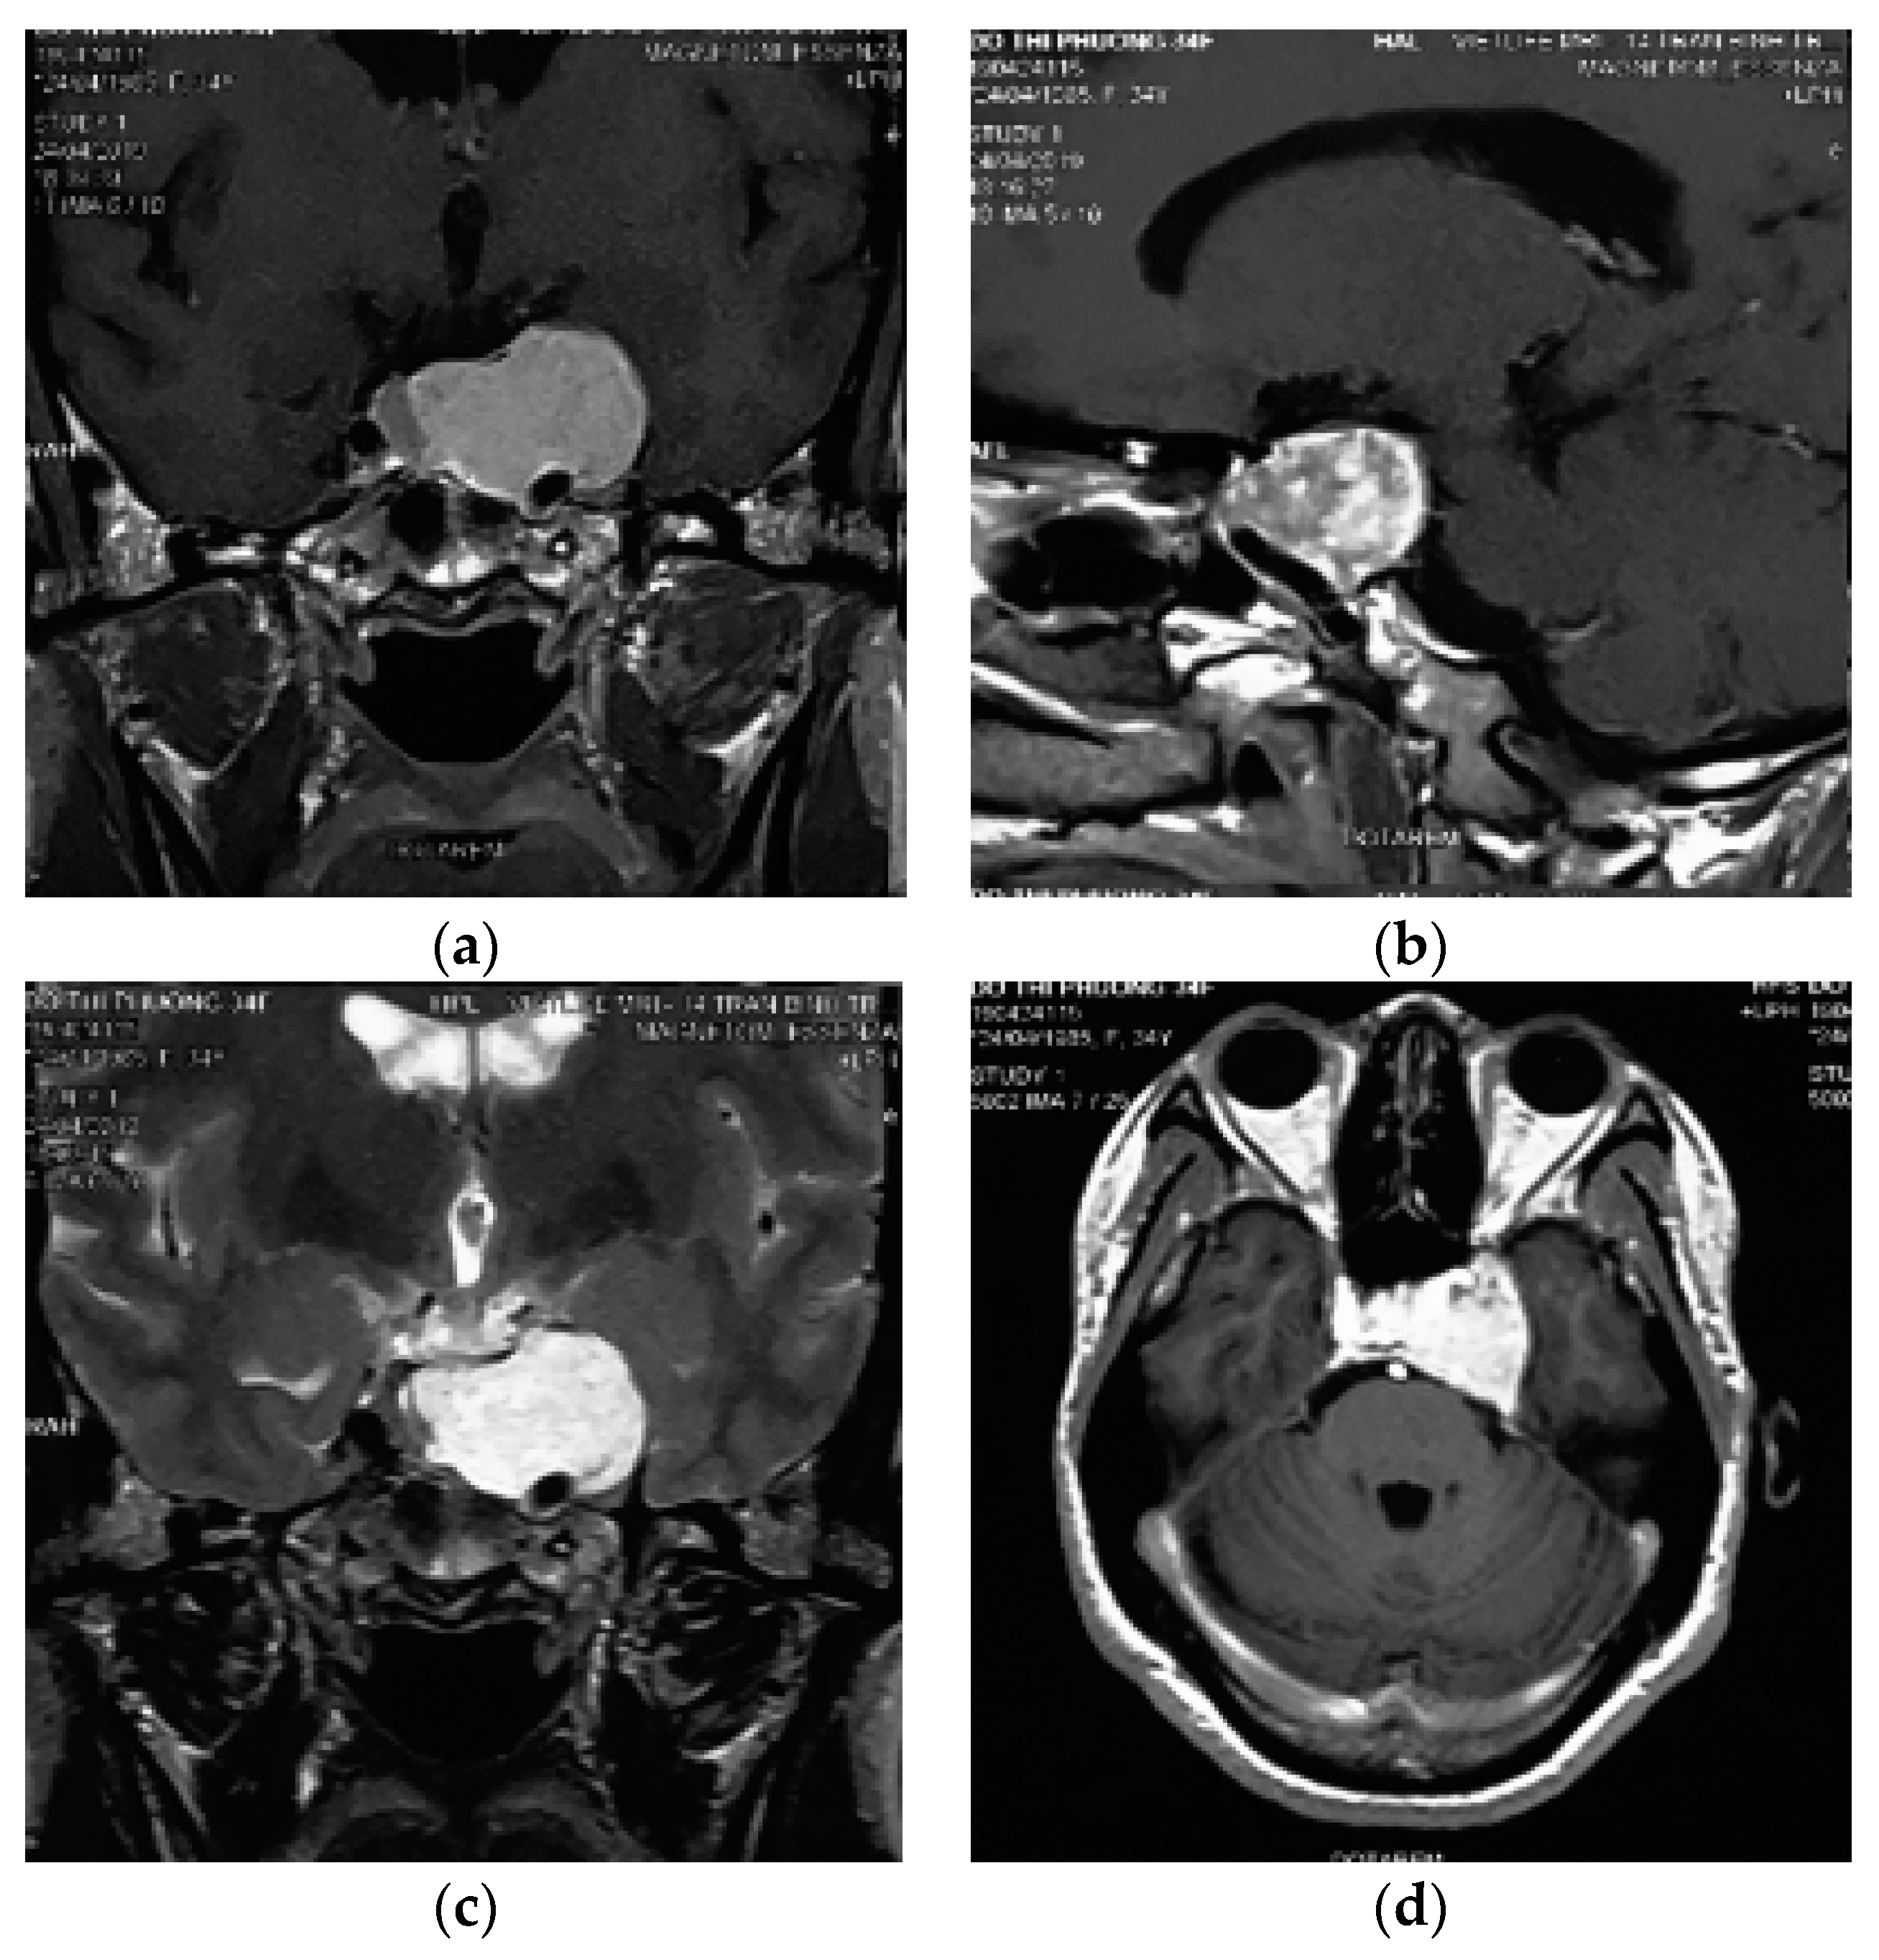

2. Case Presentation